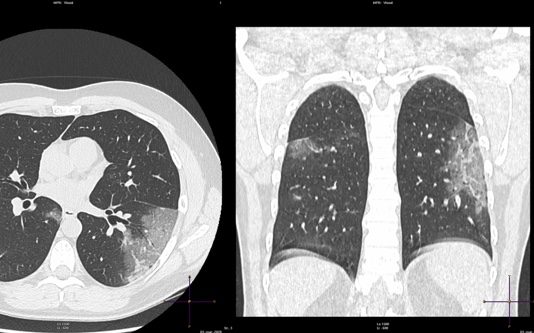

Uomo 57 anni, nessuna comorbidità nota.

Febbre e tosse non produttiva.

Leucocitosi. Insufficienza respiratoria ipossemica e ipocapnica.

Sospetto contatto con soggetti zona rossa. Tampone positivo NCOV 19.

HRTC Torace